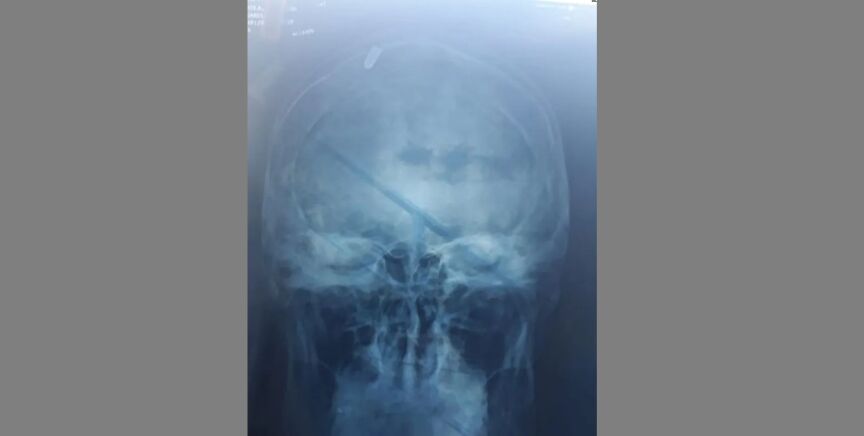

Harto de la situación, el joven decidió ir de nuevo al médico y, tras explicar lo que había pasado, decidieron hacerle una radiografía.

Cuando los médicos comprobaron lo que realmente había ocurrido, apenas podían creer lo que veían sus ojos. Leonardo Oyola tenía una bala alojada en el interior de su cabeza, el proyectil perdido había impactado casualmente en él.